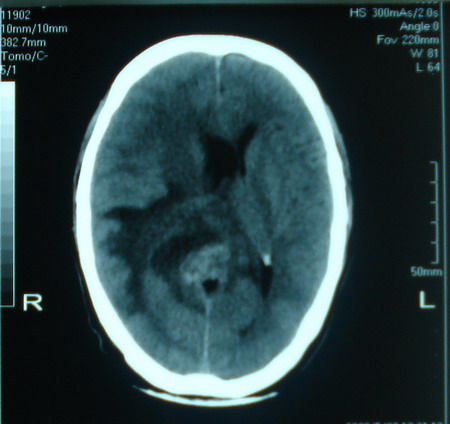

标题: CT13794:M63Y,头颅CT平扫

男,63岁,头痛,呕吐,意识模糊一周。无发烧及感染史。

小肿瘤大水肿,考虑转移瘤

脑肿瘤 1 室管膜瘤 2 转移瘤

考虑为:胶质瘤可能性大,不排除转移瘤。建议:行进一步检查。

支持右侧丘脑恶性胶质母细胞瘤可能性大,建议增强进一步检查。